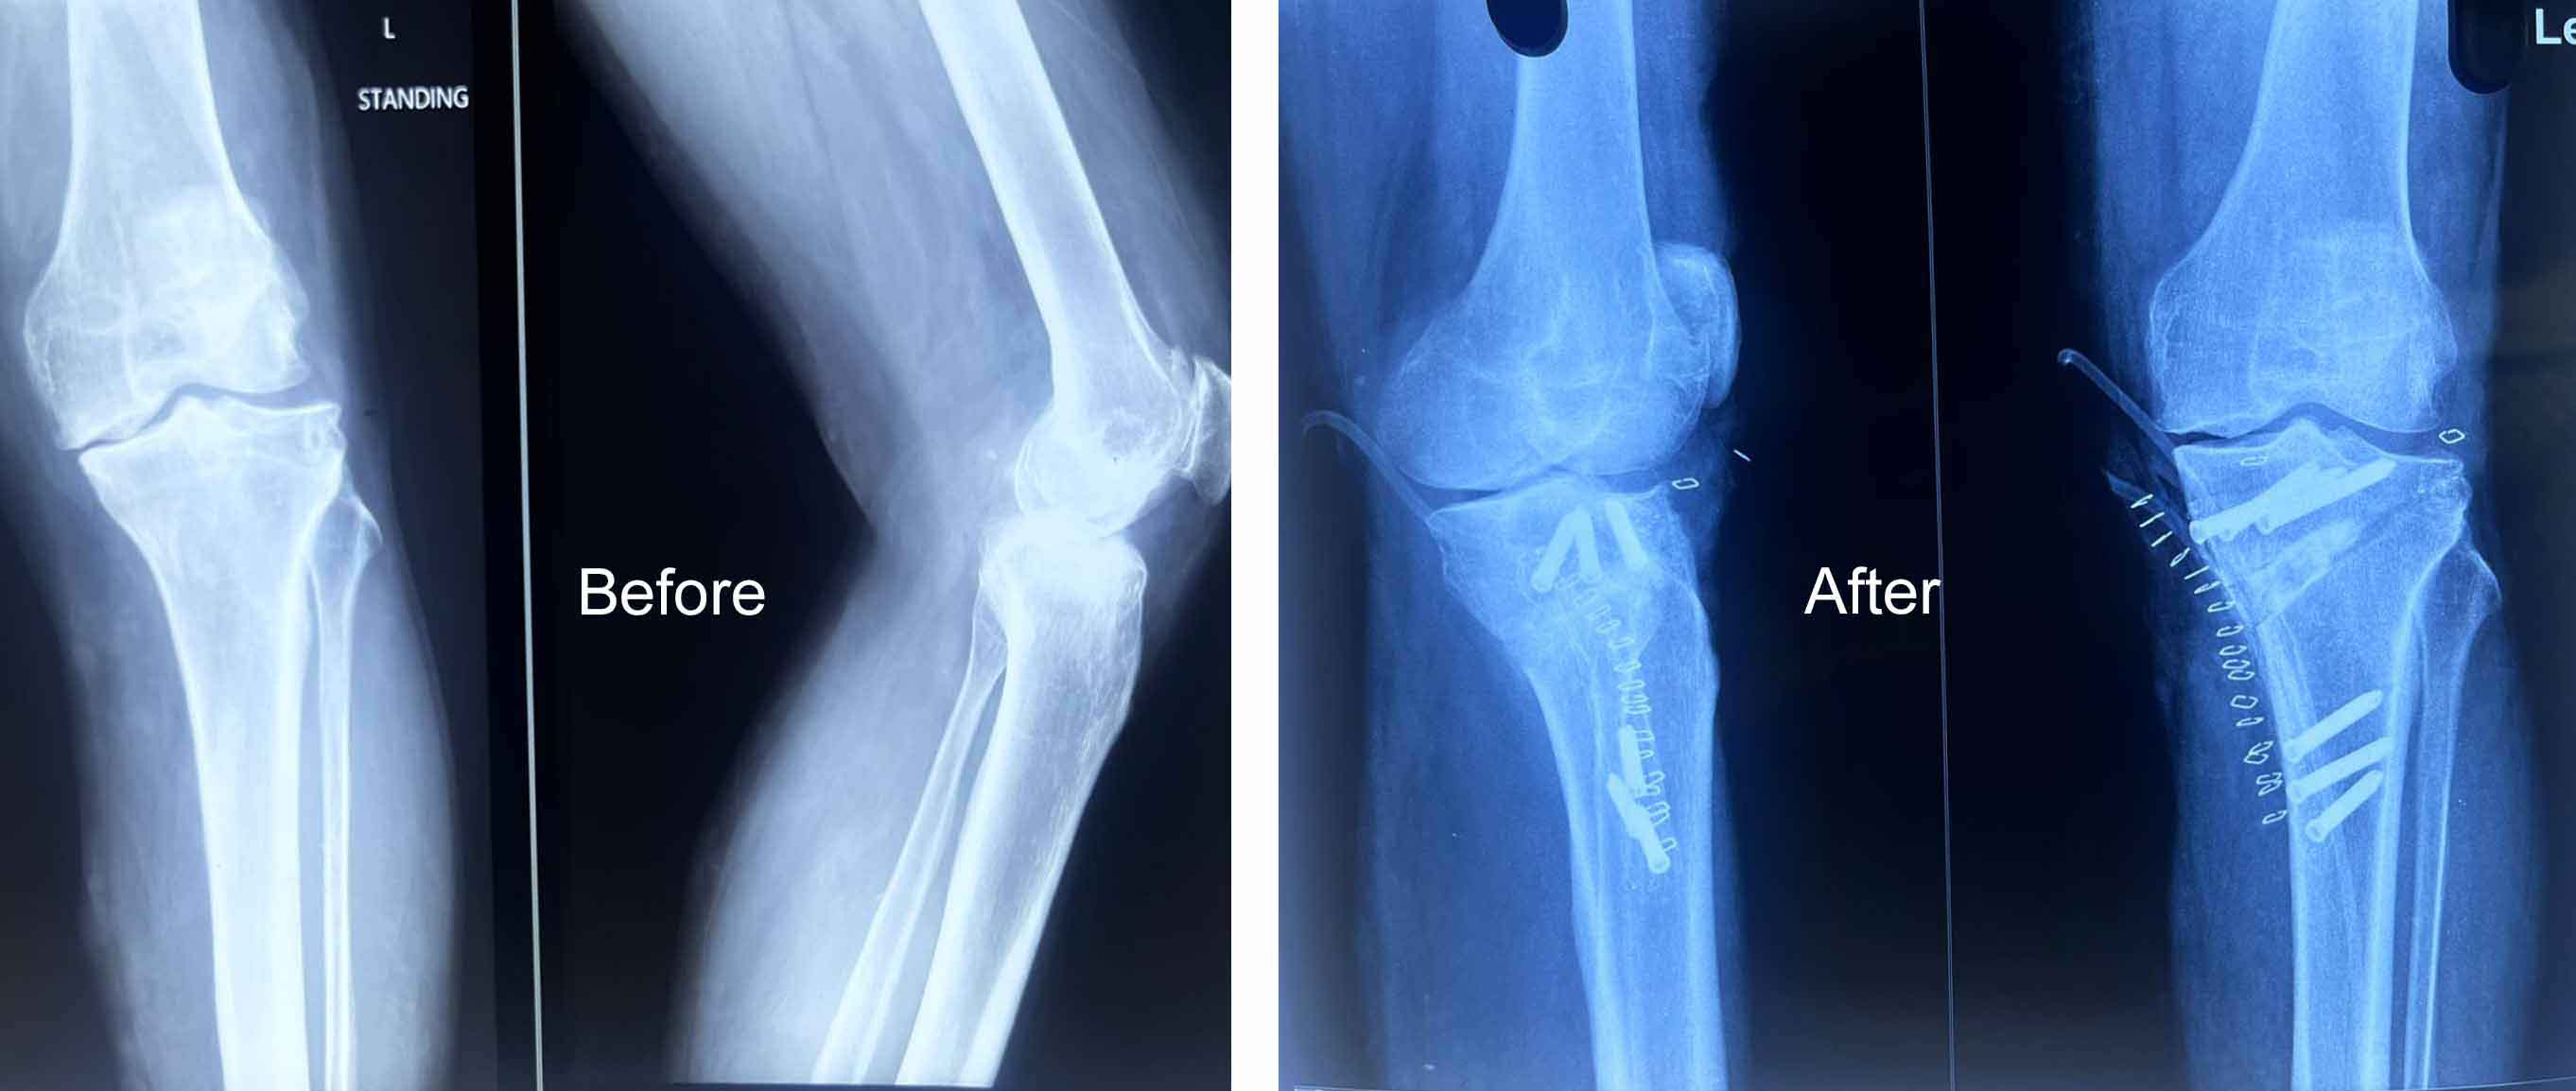

Dr Muhammed Riyadh is a distinguished medical professional in the field of orthopedics, has made significant contributions to the healthcare industry through a career marked by expertise, compassion, and unwavering dedication to patient well-being

Gallery